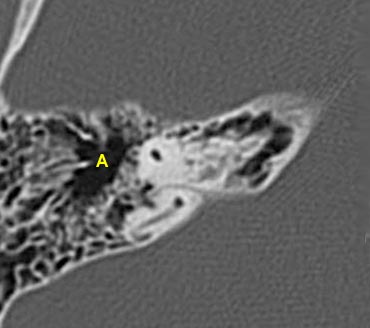

- A = Hang chũm (Antrum)

Đoạn mê đạo của dây thần kinh mặt xuất phát từ ống tai trong, chạy gần như vuông góc với trục dài của xương đá về phía trước để đến hạch gối (geniculate ganglion).

Tại hạch, dây thần kinh mặt tạo thành một vòng chữ U (gối thứ nhất của dây thần kinh mặt) để chạy ra phía sau như đoạn nhĩ dọc theo thành trong của thượng nhĩ.